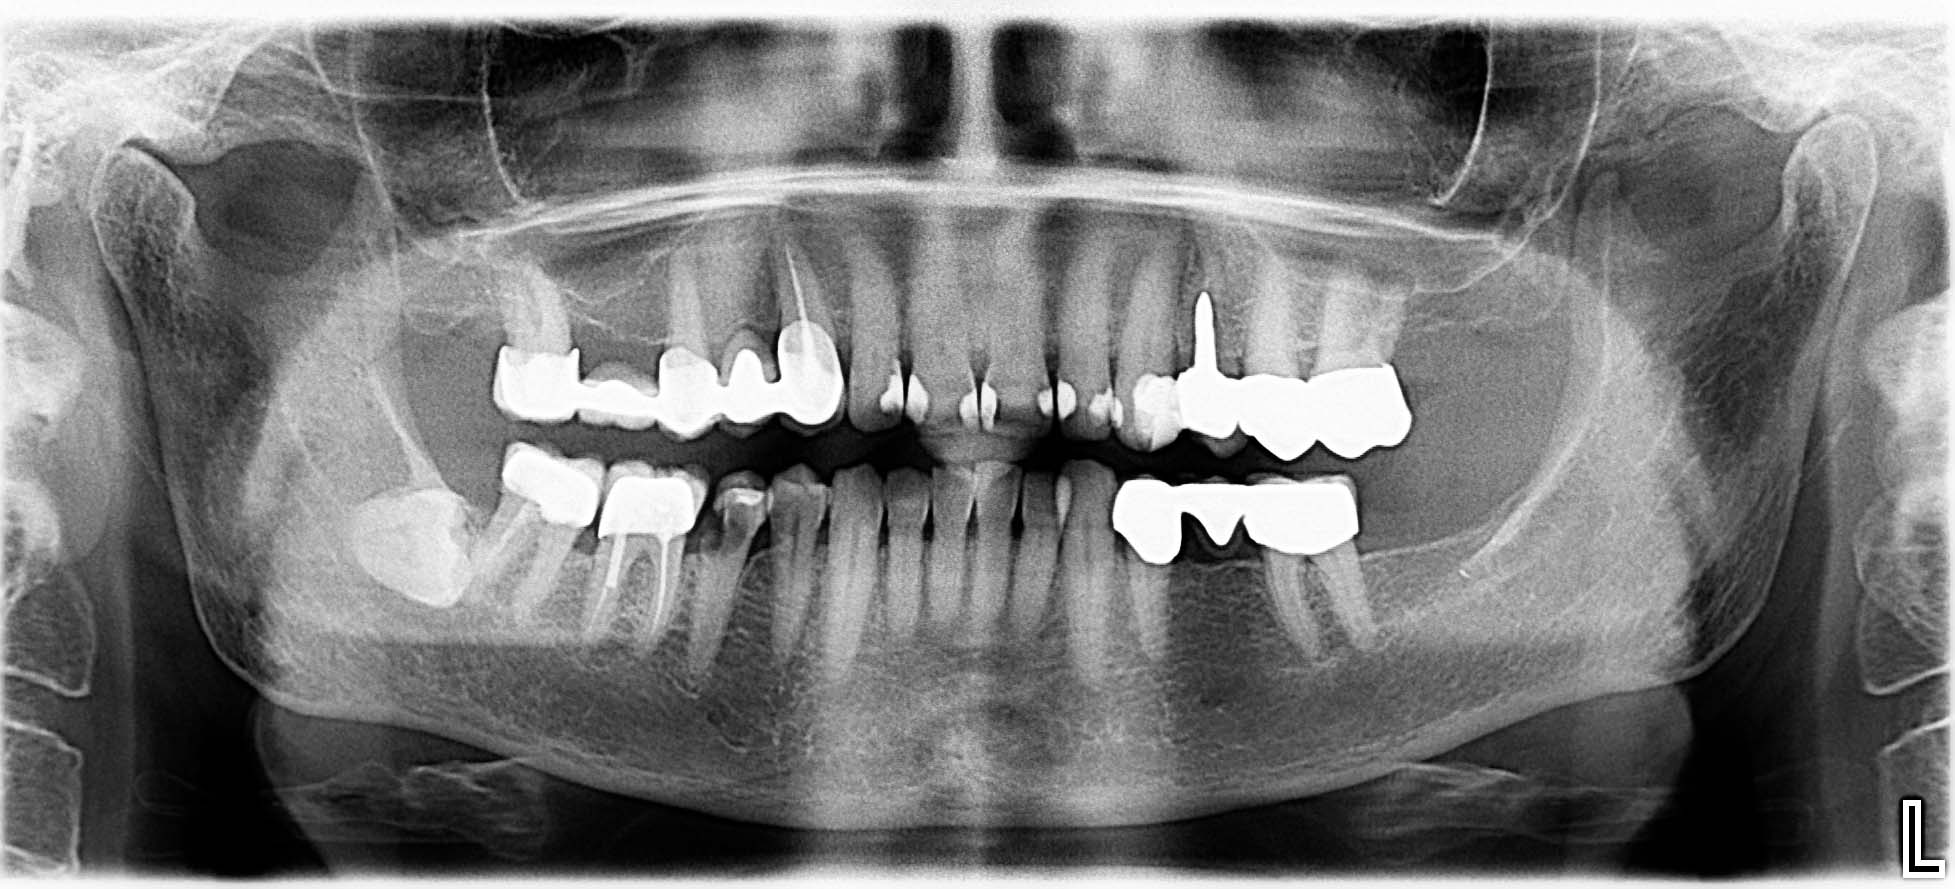

Ausgangssituation: Zahn 36 mit apikaler Beherdung, nicht erhaltungswürdig